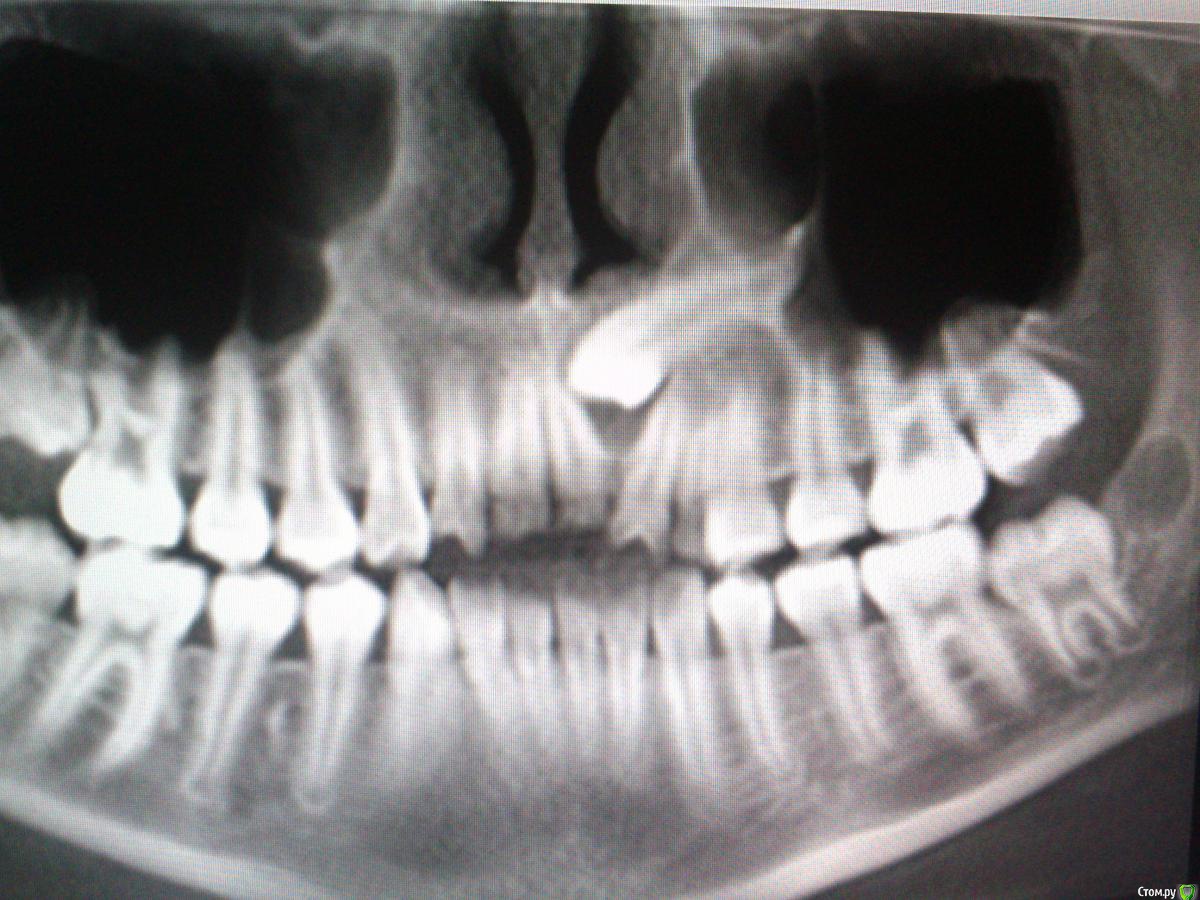

GoDemon Опубликовано 1 мая, 2015 Поделиться Опубликовано 1 мая, 2015 Здравствуйте, коллеги! Доктор - ортодонт дала данные клкт пациентки (10 лет), которой планируется ортодонтическое вытяжение клыка. От меня требовалось создать доступ. Но возник вопрос, что за тень- образование в области коронки клыка ??? думал, что, возможно, фолликулярная киста, но зуб полностью сформирован, хотя видно, что корни 2.1 и 2.2 расходятся( то ли клык их раздвинул, то ли образование вокруг него так их смещает). Так что уверенности на счет фолликулярной кисты нет, может просто остатки фолликула??? Хотелось бы услышать ваше мнение по поводу диагноза и тактику при раскрытии зуба ( если это окажется возможным делать) - просто создать доступ или все там хорошенько вычистить при раскрытии??? Спасибо. Ссылка на комментарий

krokomot Опубликовано 1 мая, 2015 Поделиться Опубликовано 1 мая, 2015 Чет я не пойму резцы что молочные? и их как-то много 5 штук. Куда ортодонт собирается вытягивать клык?, пока нет места он никуда не пойдет вы жего не ветибулярно собираетесь вытягивать? Что ворту? что остается? что уходит? И дайте срезов кт. Ссылка на комментарий

GoDemon Опубликовано 1 мая, 2015 Автор Поделиться Опубликовано 1 мая, 2015 (изменено) Чет я не пойму резцы что молочные? и их как-то много 5 штук. Куда ортодонт собирается вытягивать клык?, пока нет места он никуда не пойдет вы жего не ветибулярно собираетесь вытягивать? Что ворту? что остается? что уходит? И дайте срезов кт.В рот сам не заглядывал. По кт постоянные резцы и молочный клык слева, уже постоянный прикус. Если есть возможность тянуть ретенированный зуб, то временный клык пойдет на выход, соответственно, будут ставить брекеты. Какие еще срезы нужны??? что на них должно быть видно? Постараюсь загрузить. Изменено 1 мая, 2015 пользователем GoDemon Ссылка на комментарий

natan. Опубликовано 21 мая, 2015 Поделиться Опубликовано 21 мая, 2015 если радиус радиолюцентного образов-я видимого на снимке меньше 3- 4 мм то некоторые авторы считают что это enlarged follicle Ссылка на комментарий